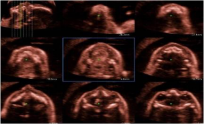

* 多切面显示模式&STIC模式:

* Omni-view成像:任意展示解剖切面,增加诊断信息